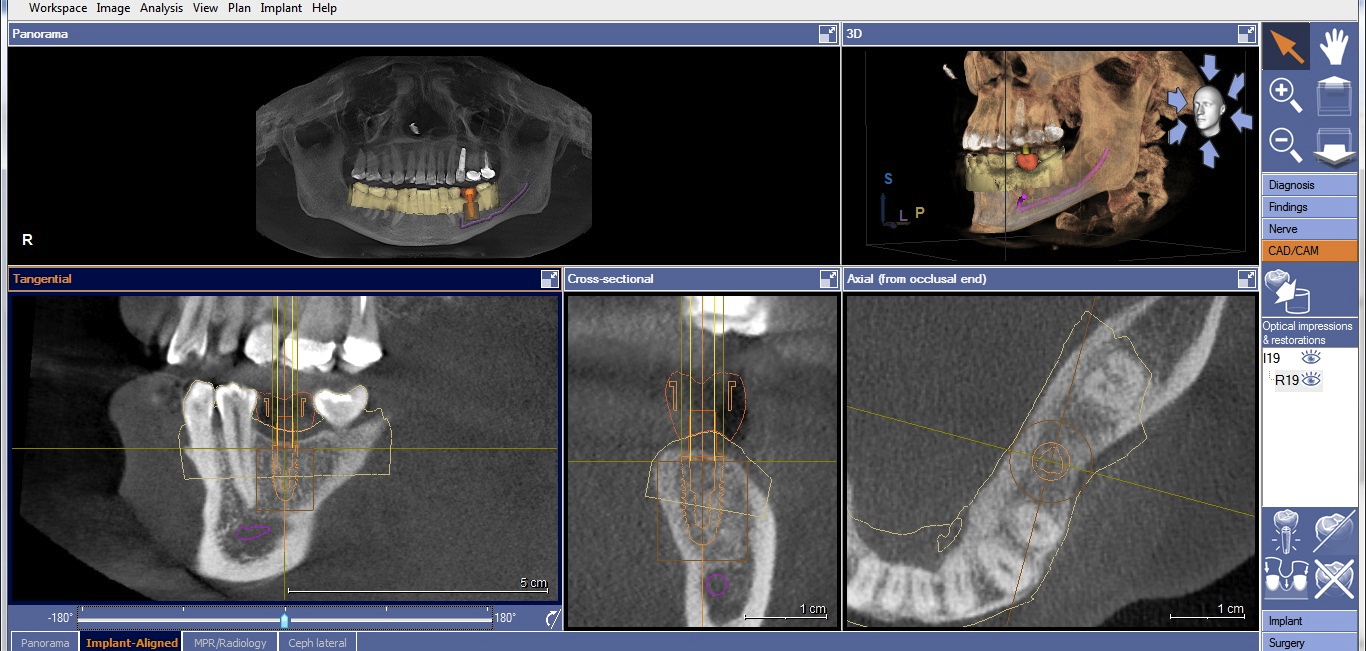

Once the desired restorative outcome is in a digital format, the patient’s CBCT scan is opened in the implant-planning software. If the edentulous space is in the posterior mandible, the inferior alveolar nerve bundle (IANB) is traced so that it is highlighted and avoided by the planned implant (Figure 2). Now, the patient’s digital restoration can be imported. Once imported, most software requires the user to identify corresponding landmarks on the digitized model and on the CBCT to merge the two data sets. It is best to avoid using teeth with crowns or large restorations as landmarks, because they cause distortions in CBCT scans and may result in inaccuracies in data set merges. Once complete, merge accuracy is verified by the user and is either confirmed or reset.

The software can now plan ideal implant placement based on the proposed restoration. The tooth being replaced will need to be identified, along with the implant brand/line, diameter, and length. Once the software digitally positions the implant, it can be repositioned, its length and width changed, and the implant line can also be changed.

Two factors affect implant depth: distance to the proximal contact and surrounding the implant with 1 mm of bone. The implant platform should be 5 mm or less from the proximal contact for proper papilla formation.21,22 Accounting for prosthetic components, the distance to the occlusal surface should be approximately 7 mm (5 mm abutment + 2 mm ceramic). If placing the restorative platform at the osseous crest does not provide this space, it is necessary to remove bone so the implant can be submerged to proper depth. However, if placing the platform 7 mm from the restorative surface does not result in surrounding the implant with 1 mm of bone, a decision must be made. The deficiency will usually be on the facial. The practitioner must either submerge the implant until there is sufficient bone surrounding it, or if this places the implant too deeply, augment the ridge prior to implant placement. Current guided regeneration techniques can predictably gain up to 5.5 mm horizontally23 and 10 mm to 12 mm vertically.24 Once the implant platform is set, the final apical length of the implant can be adjusted and the digital plan is complete (Figure 3).

Cone-beam computed tomography (CBCT) with traced and highlighted inferior alveolar nerve bundle (IANB).

Figure 2

CBCT with final implant plan. Note the digital restoration, TiBase abutment, and highlighted IANB.

Figure 3